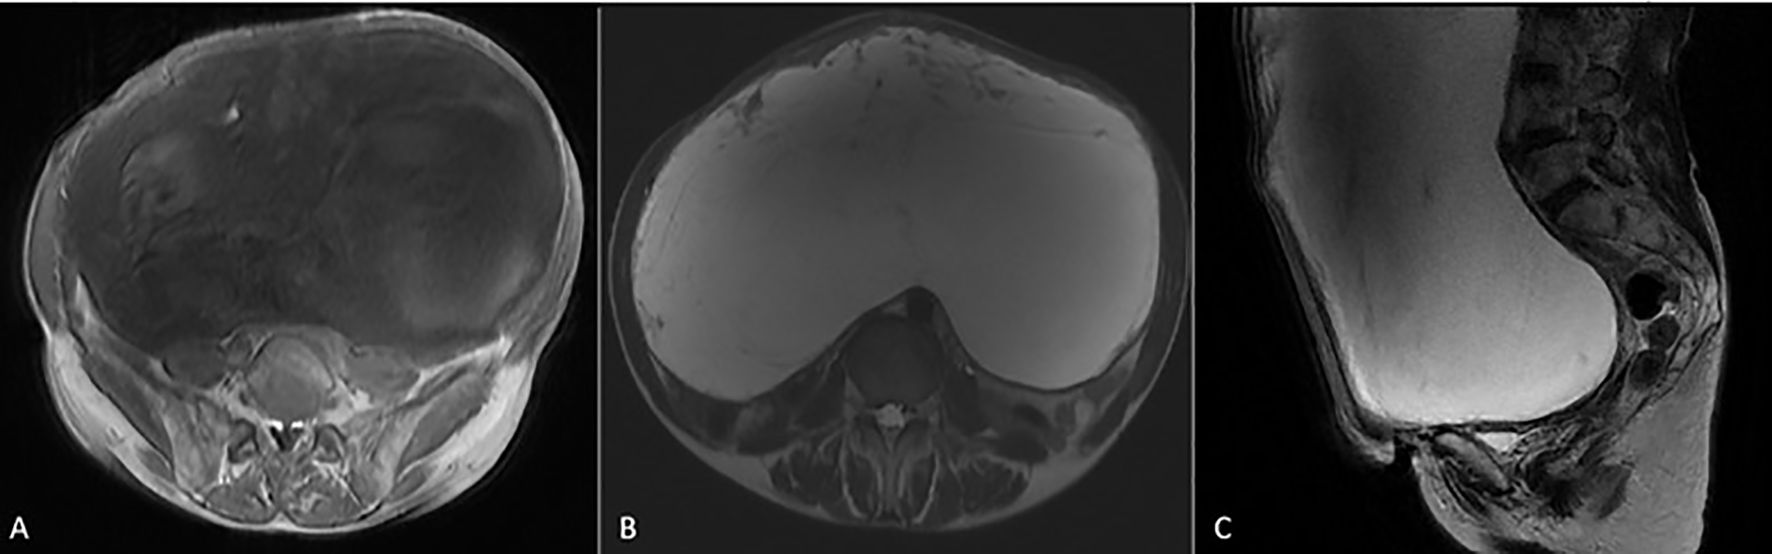

Abdominal ultrasound (US) showed a huge cystic mass occupying most of the abdominal cavity. Fatty liver infiltration with inhomogeneous parenchyma without dilatation of the intrahepatic biliary system, without cirrhosis, as well as microlithiasis of the kidneys with pelvicalyceal dilatation, especially on the right side, and abundant ascitic fluid in the peri-hepatic, hepato-renal, and peri-splenic spaces and in the pouch of Douglas were additional US findings. Computed tomography (CT) of the chest, abdomen, and pelvis showed a large complex cystic mass with calcifications occupying the entire abdomen and pelvis, causing compression of the adjacent abdominal organs. Intravenous contrast showed thick, enhancing septations. The ovaries and cervix were not visible due to displacement and compression. There was no evidence of intra-thoracic metastases or enlarged lymph nodes. Magnetic resonance imaging (MRI) of the abdomen and the pelvis revealed occupation of the greatest part of the abdomen and the pelvis by a huge abdominopelvic complex cystic mass, with a small number of solid parts and thick septations, as well as ascitic fluid in the pouch of Douglas. The mass measured approximately 27.7 cm in transverse diameter, 19 cm in anterolateral diameter, and 32 cm in cephalocaudal diameter (Figures 2A–C). Cytological examination was negative for malignancy, showing only rare mesothelial cells and sparse lymphocytes.

Figure 2. MRI images of the giant hydropic leiomyoma (HLM). (A) T1-weighted image showing the leiomyoma with low-to-intermediate signal intensity, reflecting the tumor’s solid components. (B) T2-weighted image demonstrating high signal intensity within the leiomyoma, indicative of significant fluid accumulation due to hydropic degeneration. (C) T2-weighted MRI in the sagittal plane showing a large HLM with high signal intensity. The mass causes significant mass effect on adjacent organs, displacing the bladder anteriorly and compressing the rectum posteriorly.

Despite the presence of imaging findings that raised suspicion for malignancy—such as the tumor’s large size, thick internal septations, and the presence of ascites—several characteristics supported a benign diagnosis. On MRI, the lesion demonstrated well-circumscribed margins without infiltrative behavior, and there were no signs of lymphadenopathy, necrosis, or peritoneal deposits. The solid components showed no irregular or intense enhancement, and the T2-weighted hyperintensity correlated with significant fluid accumulation rather than tumoral aggressiveness. These findings, when combined with normal CA-125 and the absence of systemic symptoms, favored a diagnosis of a benign but atypically degenerating uterine mass. Nonetheless, due to the size, mass effect, and residual diagnostic uncertainty, surgical resection was deemed necessary by the multidisciplinary team.

The imaging and histologic findings in this case show a clear radiologic–pathological correlation. On MRI, the lesion demonstrated marked T2-weighted hyperintensity (Figures 2B, C), which corresponds to the extensive stromal edema and cystic fluid accumulation seen histologically—hallmark features of hydropic degeneration. Additionally, the compartmentalized, nodular architecture identified on microscopic examination explains the septated and multilocular appearance of the tumor on imaging. Grossly, the tumor’s smooth, lobulated external surface (Figure 3A) supports its benign, encapsulated nature. Immunohistochemical staining further confirmed a smooth muscle origin (desmin+, SMA+, and calponin+) with low proliferative activity (Ki-67 < 5%), consistent with a diagnosis of benign hydropic leiomyoma and excluding high-grade malignancy.

HLMs may present on MRI with imaging features that overlap with malignant tumors, particularly leiomyosarcoma, endometrial stromal sarcoma, and ovarian cystic malignancies. Common features that raise suspicion for malignancy include large size, thick septations, cystic-solid architecture, and associated ascites. In our case, these characteristics necessitated careful preoperative evaluation and tumor board discussion (11). However, several radiologic findings were more suggestive of a benign process. These included the well-defined tumor margins, lack of infiltrative behavior, absence of intratumoral necrosis, and no evidence of pelvic or para-aortic lymphadenopathy or peritoneal nodules. Additionally, there was no enhancement of solid components in a pattern typical of aggressive sarcomas. The T2-weighted hyperintensity corresponded histologically to interstitial fluid accumulation and stromal edema, which are hallmark features of hydropic degeneration. Together, these imaging characteristics—although atypical—favored the diagnosis of a benign but degenerative leiomyoma, supporting the decision to proceed with surgical management. To further assist in differential diagnosis, a comparative summary of radiologic and clinical features distinguishing HLM from other cystic abdominopelvic masses is presented in Table 2.